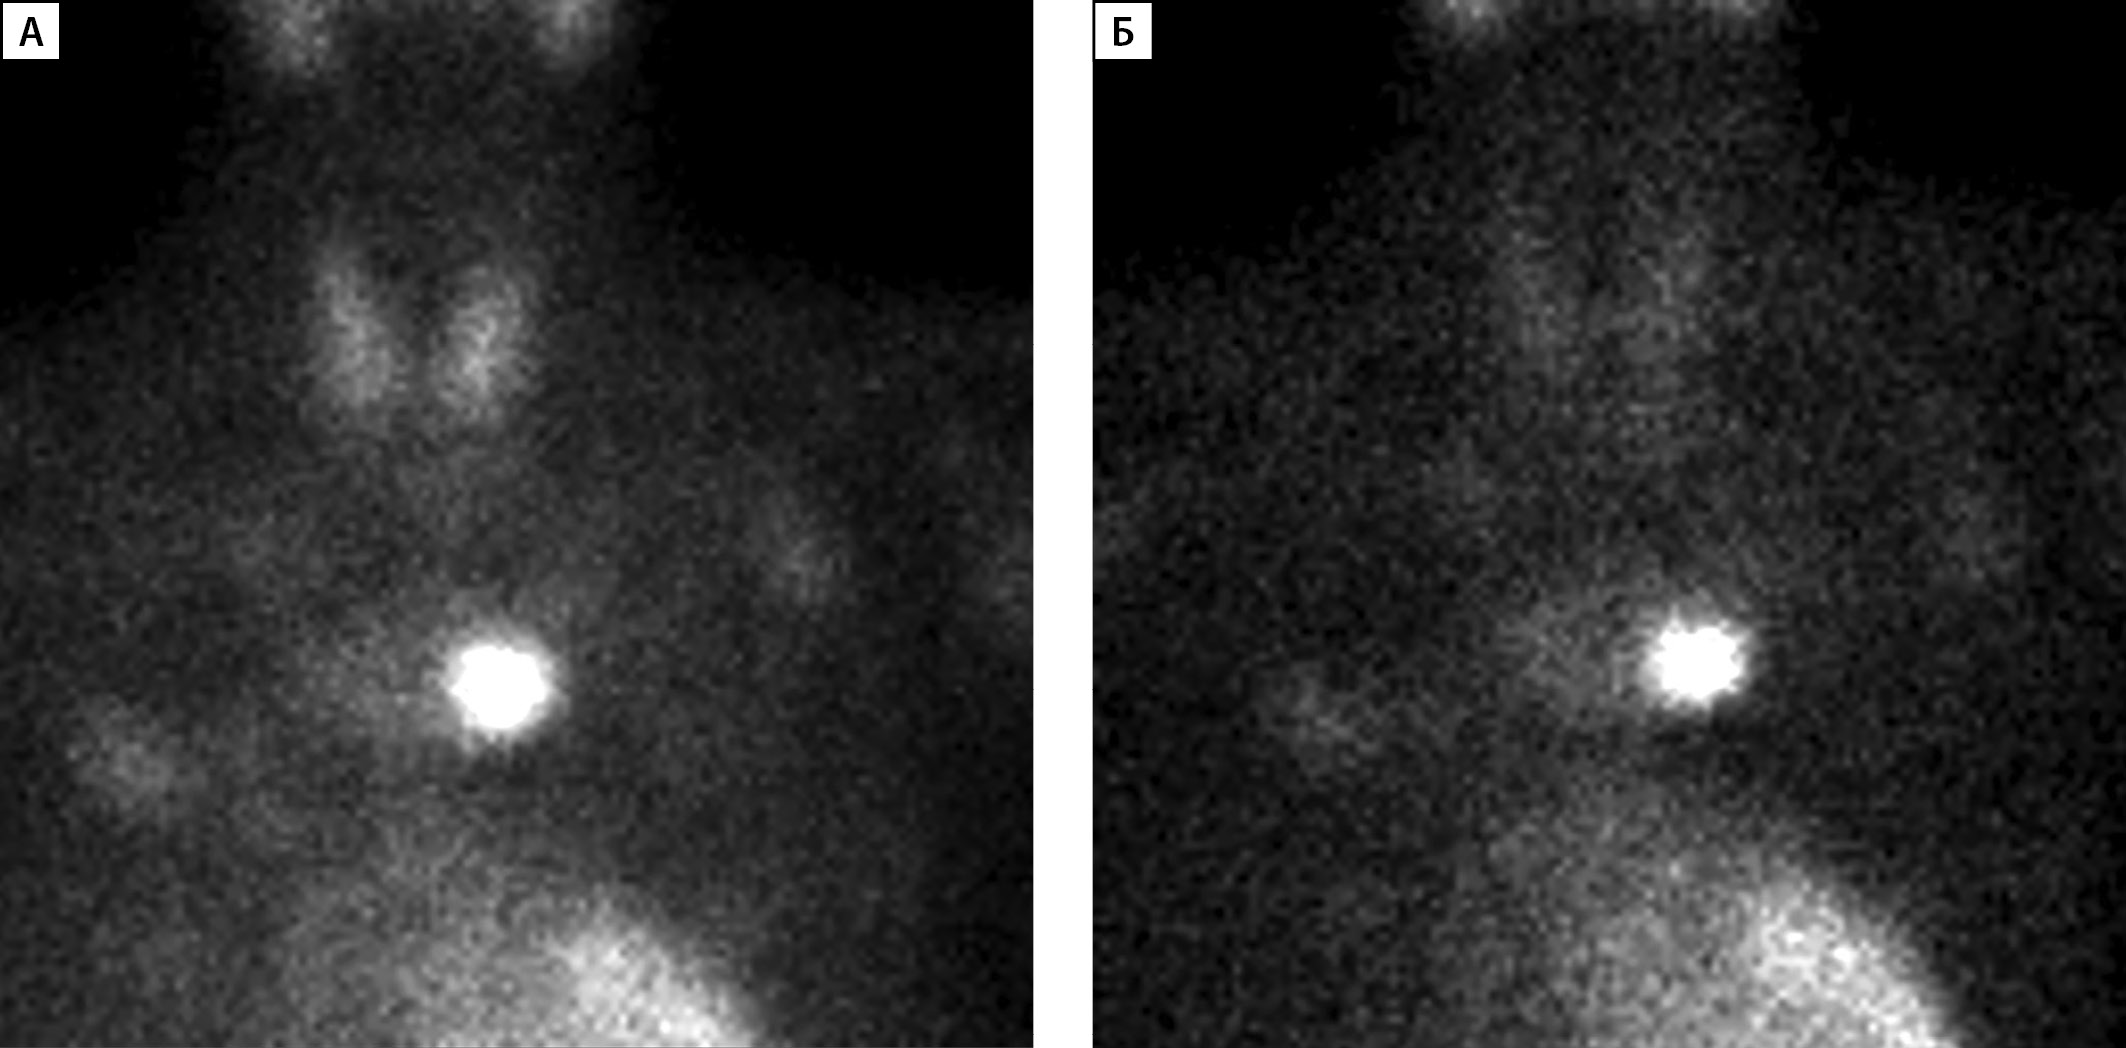

Сцинтиграфия с ОФЭКТ-КТ проведена 33 пациентам, среди них у 26 человек данные сцинтиграфии совпали с результатами УЗИ. У 2 детей по результатам сцинтиграфии выявлены множественные образования ОЩЖ, которые не визуализировались на УЗИ. У 5 пациентов выявлено эктопическое расположение образования ОЩЖ (табл. 2): у 3 пациентов образование было локализовано в ткани щитовидной железы (табл. 2, рис. 2), у 2 — в средостении. У одного из них (пациент №3, рис. 3) данные УЗИ были интерпретированы как образования нижних ОЩЖ, однако при выполнении сцинтиграфии аденома располагалась в области средостения.

Рисунок 3 (А, Б). Планарная сцинтиграфия образования околощитовидной железы,

эктопированного в средостение.

А — Через 15 минут после введения контраста;

Б — через 90 минут после введения контраста.

У одного из пациентов (табл. 2, пациент №3) при проведении УЗИ ОЩЖ выявлены образования левой и правой нижних ОЩЖ, однако, по результатам сцинтиграфии и МСКТ, образование ОЩЖ располагалось в области средостения (рис. 3). Таким образом, сцинтиграфия с ОФЭКТ-КТ, а в некоторых случаях и МСКТ являются предпочтительными методами визуализации образований ОЩЖ.